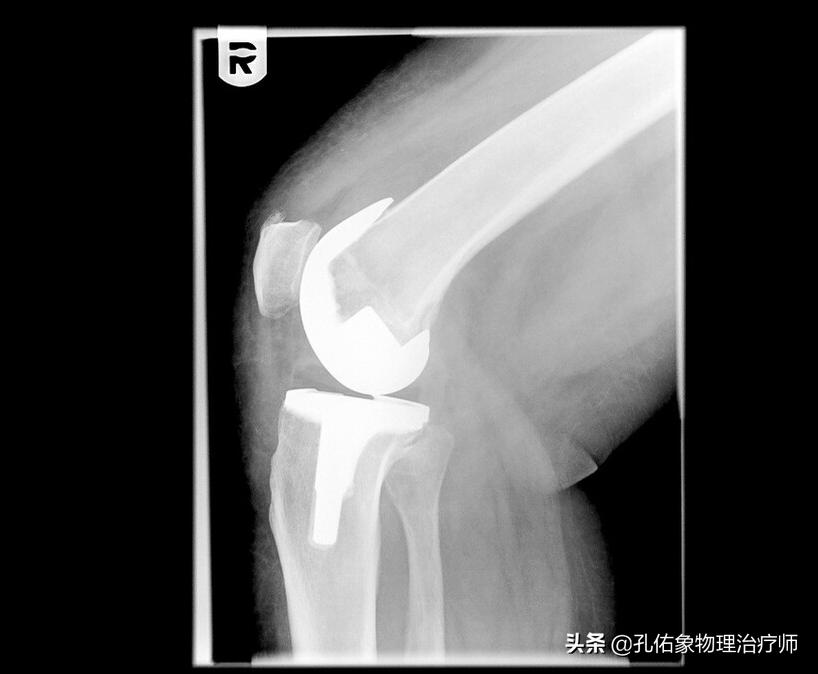

4.若是已经发展到关节炎,说明软骨已经退变很严重,要想再来恢复损伤的软骨,从目前的医疗水平而言,基本不可能。倘若已经严重影响您的生活质量,目前最常见的处理方式是关节置换。

骨性关节炎是在软骨软化严重的基础上发生的,一旦出现软骨磨损特别严重,您做任何动作都会出现疼痛,会严重影响您的生活质量,不能正常进行上下楼梯、下蹲起身,刺激滑膜产生关节内的积液、肿胀,甚至关节变形。